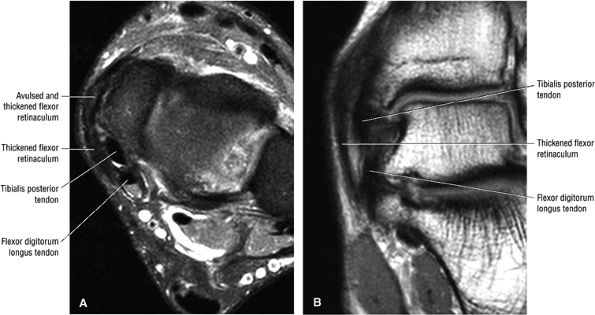

FIGURE 5.131 ● Chronically scarred flexor retinaculum. Dislocation of the tibialis posterior is associated with a torn flexor retinaculum. The retromalleolar groove may also be shallow. (A) Axial FS PD FSE image. (B) Coronal T1-weighted image.

Type 1: There is tendon hypertrophy with heterogeneous signal intensity in intrasubstance vertical splits (Fig. 5.130). Associated findings include increased signal intensity (intrasubstance striations) and girth at the distal tendon insertion to the navicular (a normal variant), osseous spurring with or without fatty marrow signal in the posteromedial aspect medial malleolus (see Fig. 5.130), and tendon dysfunction or dislocation with disruption of the flexor retinaculum (Fig. 5.131).

The peroneal retinaculum prevents the peroneal tendons from subluxing laterally over the lateral malleolus. Tears or stripping of the peroneal retinaculum from the lateral malleolus is inferred when subluxation or dislocation of the peroneal tendons is seen lateral to the lateral malleolus.